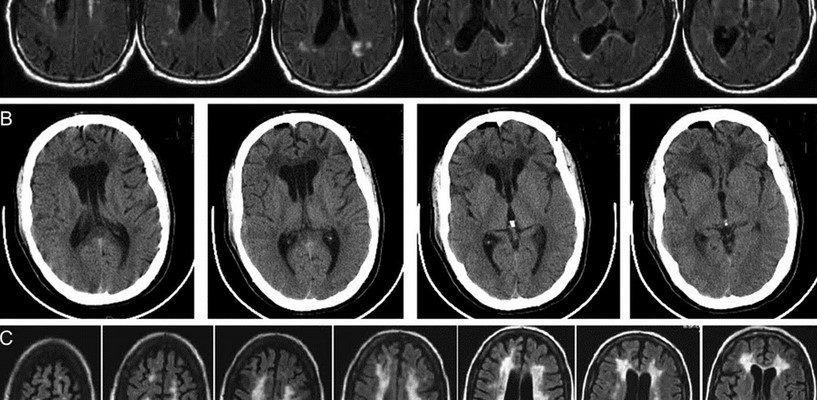

Только магнитный резонанс может диагностировать расстройства с достаточной точностью.

Этот метод позволяет четко определять объем изменения и его местоположения и, таким образом, объяснить или определить фактическую причину изменений, поскольку местоположение пожара, в отличие от симптомов, является специфическим.